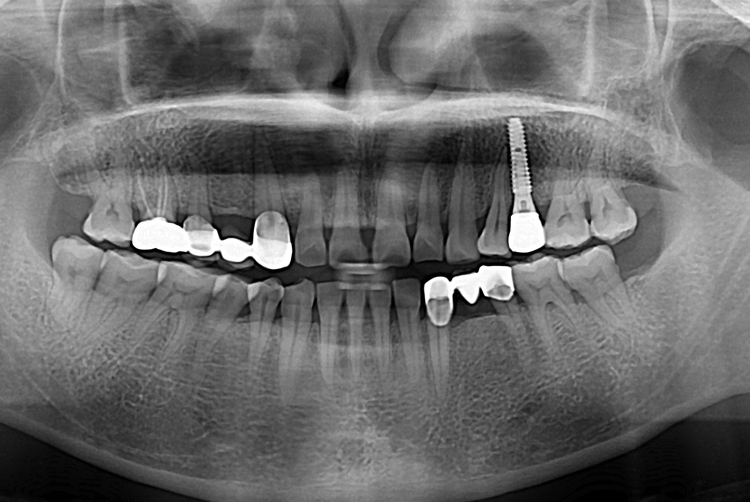

[임플란트] 어금니 임플란트

치료전 : 2018-06-13